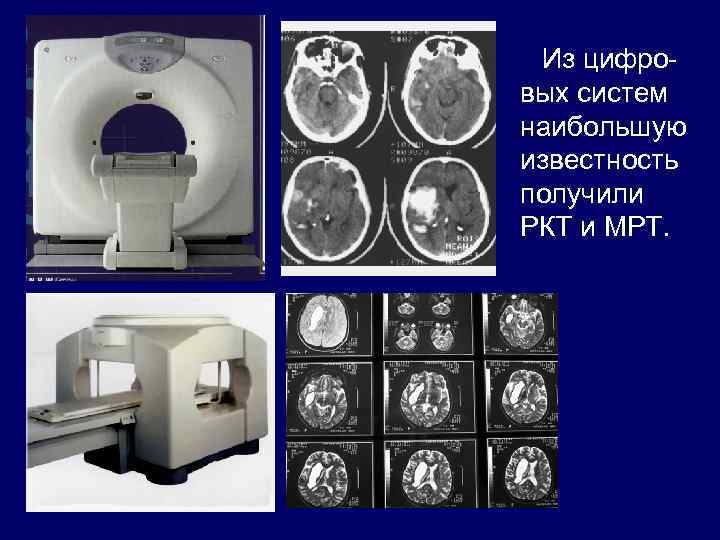

Из цифровых систем наибольшую известность получили РКТ и МРТ.

РКТ 1 2 В зависимости от модели компьютерного томографа изображения могут быть получены с той или иной резкостью. Рис 1 – томограмма головного мозга на устройствах первого поколения, Рис 2 – томограмма на относительно современном устройстве.